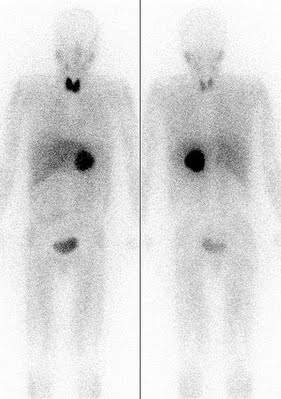

Besteht anschließend noch Unklarheit, ob ein M. Parkinson oder ein Parkinson-Syndrom vorliegt, so ist die Unterscheidung mittels MIBG-Szintigraphie möglich, weil der M. Parkinson zu einer verminderten MIBG-Darstellung des Herzens führt.

Im vorliegenden Beispiel ist bei einem Patienten mit M. Parkinson das normalerweise gut sichtbare Herz nicht mehr abzugrenzen.